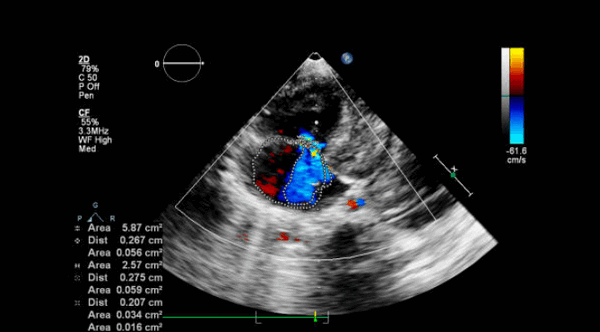

Непрерывно-волновой допплер более полезен, чем импульсный, а цветное допплеровское картирование кровотока (ЦДК) хорошо для отображения антероградных и ретроградных потоков. Турбулентный кровоток регистрируется в виде мозаики цветов. В митральных биопротезах обычно видна одна струя. В большинстве митральных механических клапанов видны 2 струи (почти равного размера у клапанов Старра - Эдвардса, одна меньше другой в клапанах Бьорка - Шайли).

При регургитации может быть несколько струй разного размера в зависимости от типа клапана (например, 2 струи у Бьорка - Шили, несколько у Старра - Эдвардса). ЦДК также помогает различать чресклапанную и парапротезную регургитацию и помогает выявить новую регургитацию.

Эхокардиография и цветное допплеровское картирование